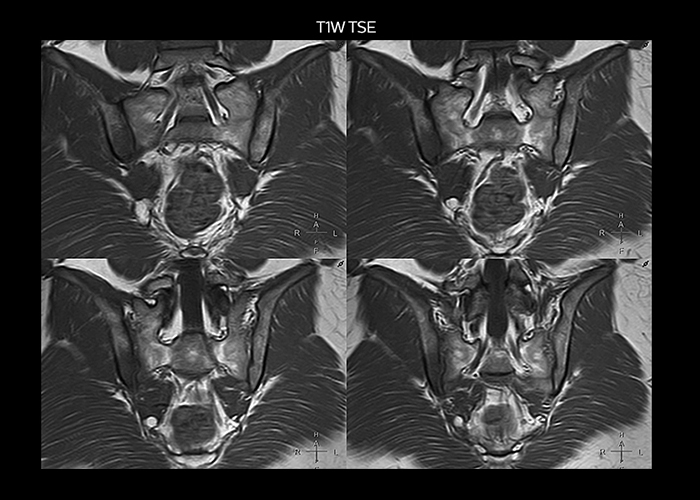

“On average, we scan about 80 patients per day, but on some days we scan well over 100 patients. The scanner is in use 7 days per week, operated 20 hours per day on week days and 8 hours per day in the weekend,” Mr. Tuna says. “To avoid coil changes we plan examinations of similar anatomies back to back, such as head and spine. Multiva helps us here a lot because coils don’t need to be changed frequently. Moreover, thanks to parallel imaging technology and 16-channel HeadSpineTorso and 8-channel MSK coils we are able to achieve excellent image quality. In this way Multiva helped us to increase both image quality and productivity.” “Neurological cases, such as brain and spine imaging, represent the largest share in our MR scanning, followed by musculoskeletal cases. In general, we use simple and basic imaging protocols. But occasionally, we use advanced techniques for problematic cases if necessary.

“Since we have Multiva, we have improved our workflow, because it has been so easy for our operators to learn and use Multiva. Our operators notice that the coils are lightweight and coils don’t need to be changed frequently. The user interface is easy to use. Features like this help us to scan a high number of patients. For instance, the musculoskeletal coils can be used interchangeably, and due to the user-friendly interface, the number of mistakes such as, for example, correct coil element selection has decreased significantly, because the system does it automatically by itself.” “Most important, Multiva satisfies our clinical imaging needs very well,” says Mr. Tuna. “Many features of Multiva have become similar to the Ingenia system. Even in more complex imaging such as abdominal and cardiac, the image quality and performance of Multiva is better than we expected. General surgeons and physicians from our hospital’s internal medicine department prefer to refer to us because of this.”

“Overall, Multiva provides what we need in term of patient needs and even potential needs,” says Mr. Tuna. “It allows us to scan a high patient volume and image a large variety of anatomies and conditions.” “Our goal is to achieve uncompromising quality based on universal standards, while solving clinically complex cases. Our Multiva scanner allows high productivity with fast imaging time, and allows us to make confident diagnoses in a broad range of cases.” “It’s an excellent multi-purpose scanner that satisfies all our MR imaging requirements in the hospital,” he concludes.